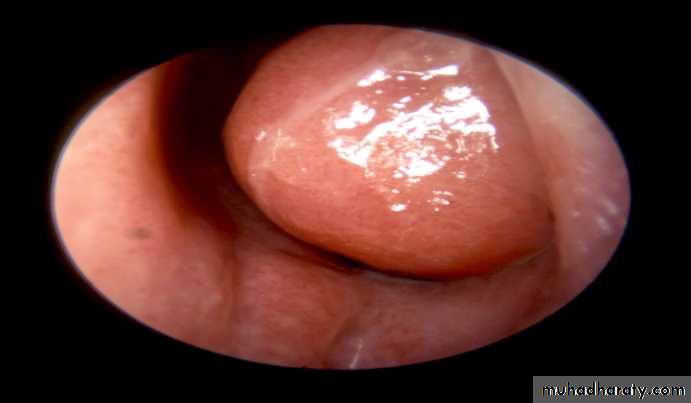

.permanent hypertrophic changes accompany the inflammatory oedema and cellular infiltration in all the constituent parts of the mucosa i.e. stroma , glands , blood vessels , and lymphatic tissue . the epithelium loses clilia and shows a tendency to squamous metaplasia . the mucosa becomes thick and nodular , especially at the extremities and free border of the the occupy the posterior choana . fibrosis can cause venous and lymphatic obstruction . if the resulting passive edema occurs in the situation where the mucosal stroma is loose , polypi form . nasal polyposis , however , usually indicate an allergic or vasomotor origin of the rhinitis , in which the polyposis results from increases capillary permeability

As for simple chronic rhinitis , with the addition of limited reduction of the hypertrophied inferior turbinate and removal of any polypi . topical decongestant preparation must be discouraged or discontinued . reduction is achieved by :